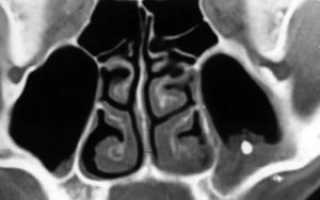

Практически в 100% случаев точно диагноз позволяет установить КОМПЬЮТЕРНАЯ томография пазух носа. Обычный рентген и МРТ дают менее информативную картину. На результатах компьютерной томографии часто можно четко увидеть и пломбу и формирующееся грибковое тело, как показано на рисунке.

Пациенты могут испытывать небольшой дискомфорт в области верхней челюсти, иногда возникает гнойный гайморит на стороне грибкового тела. И, естественно, в прошлом пациенты лечили у стоматолога верхние зубы. К сожалению, других характерных симптомом болезни просто нет.